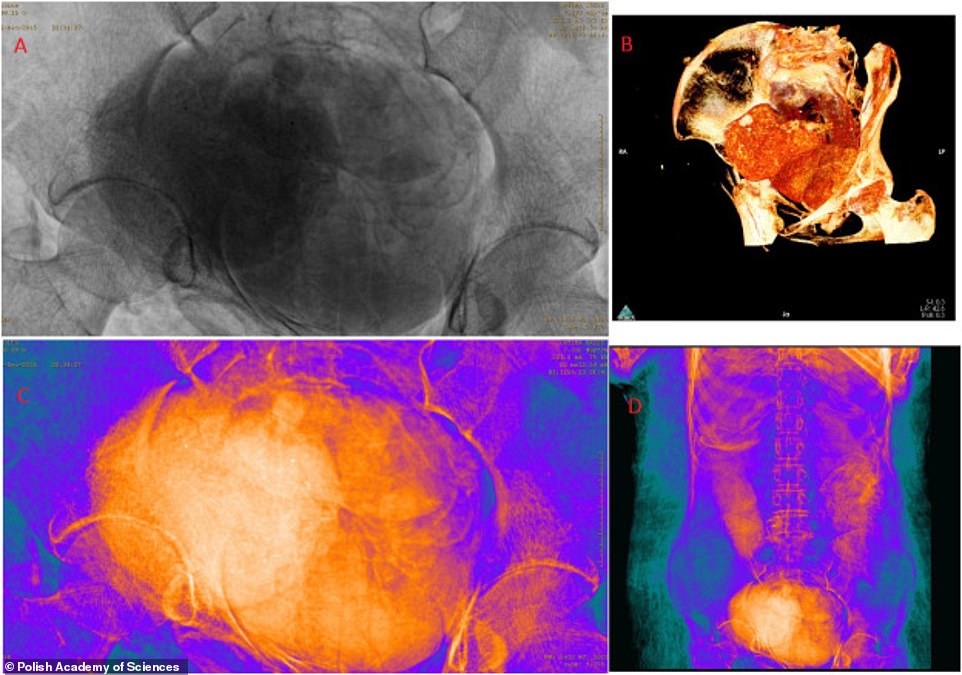

Однак комп'ютерне сканування принесло сенсаційний результат - виявилося, що в гробниці була похована жінка, яка виношувала дитину.

"Ми вже збиралися підвести підсумки проекту та відправити публікацію до друку. Мій чоловік Станіслав вирішив востаннє глянути на рентгенівські знімки, і ми побачили в животі померлої жінки знайому, як батькам трьох дітей, картину - маленьку ніжку", - повідомила доктор Маржена Ожарек-Шілке, антрополог і археолог, співавтор дослідження.

Вчені використовували безліч різних фільтрів, щоб вивчити мумію сканером, не торкаючись до неї. Було встановлено, що жінка перебувала приблизно на 26-28 тижні вагітності, плід знаходиться в положенні ембріона, стать дитини визначити не вдалося.